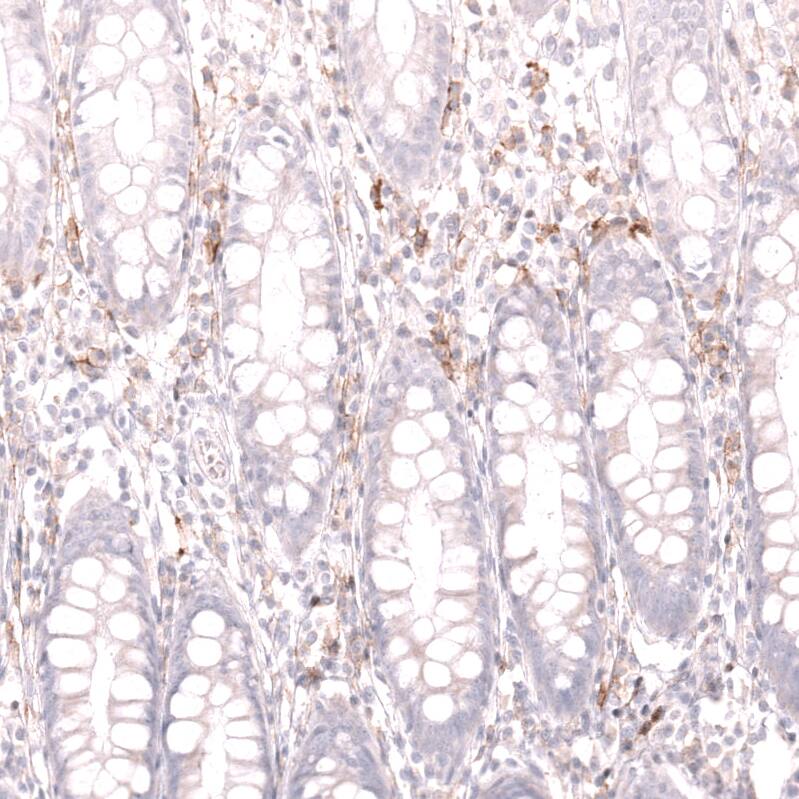

CD19 Antibody (CL15454) - Azide and BSA Free Immunohistochemistry-Paraffin: CD19 Antibody [NBP3-44277]

Immunohistochemistry-Paraffin: CD19 Antibody [NBP3-44277]

Analysis in human tonsil and kidney tissues using NBP3-44277 antibody. Corresponding CD19 RNA-seq data are presented for the same tissues.